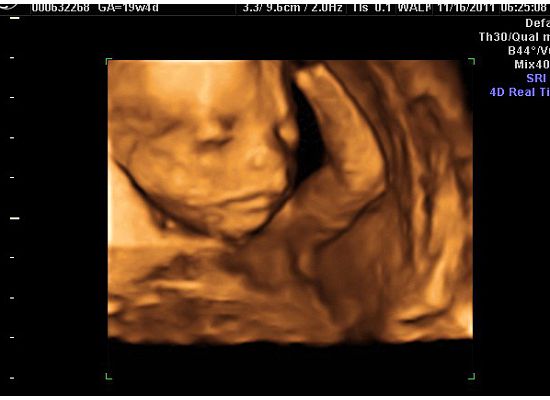

As for the scan, it went perfectly! We got to see our precious new baby and he appears to be 100% healthy. It is truly amazing what you can see via ultrasound. We go to visualize all of the major organs and even the blood flow of the major vessels. We got several 3D "face shots" although, he was buried against the placenta for many of them. He continues to still be breech, although he has lots of time to spin around. We saw him drink amniotic fluid and saw his full bladder.

We got to see his spine and visualize that it is fully enclosed, but due to his position, my tech could not get one picture that she needed, which was a cross section of his spine. She said that she can see that the spine looks perfect, but she just needed that one picture to check it off of her list. That means that I get another ultrasound at my appt on Tuesday. She said hopefully he will have moved and she can get the shot, as well as get some more pictures of his sweet face. Based on what we saw so far, he seems to resemble Jackson. It is still so early to tell, though! Check out the pictures of our hansome man!